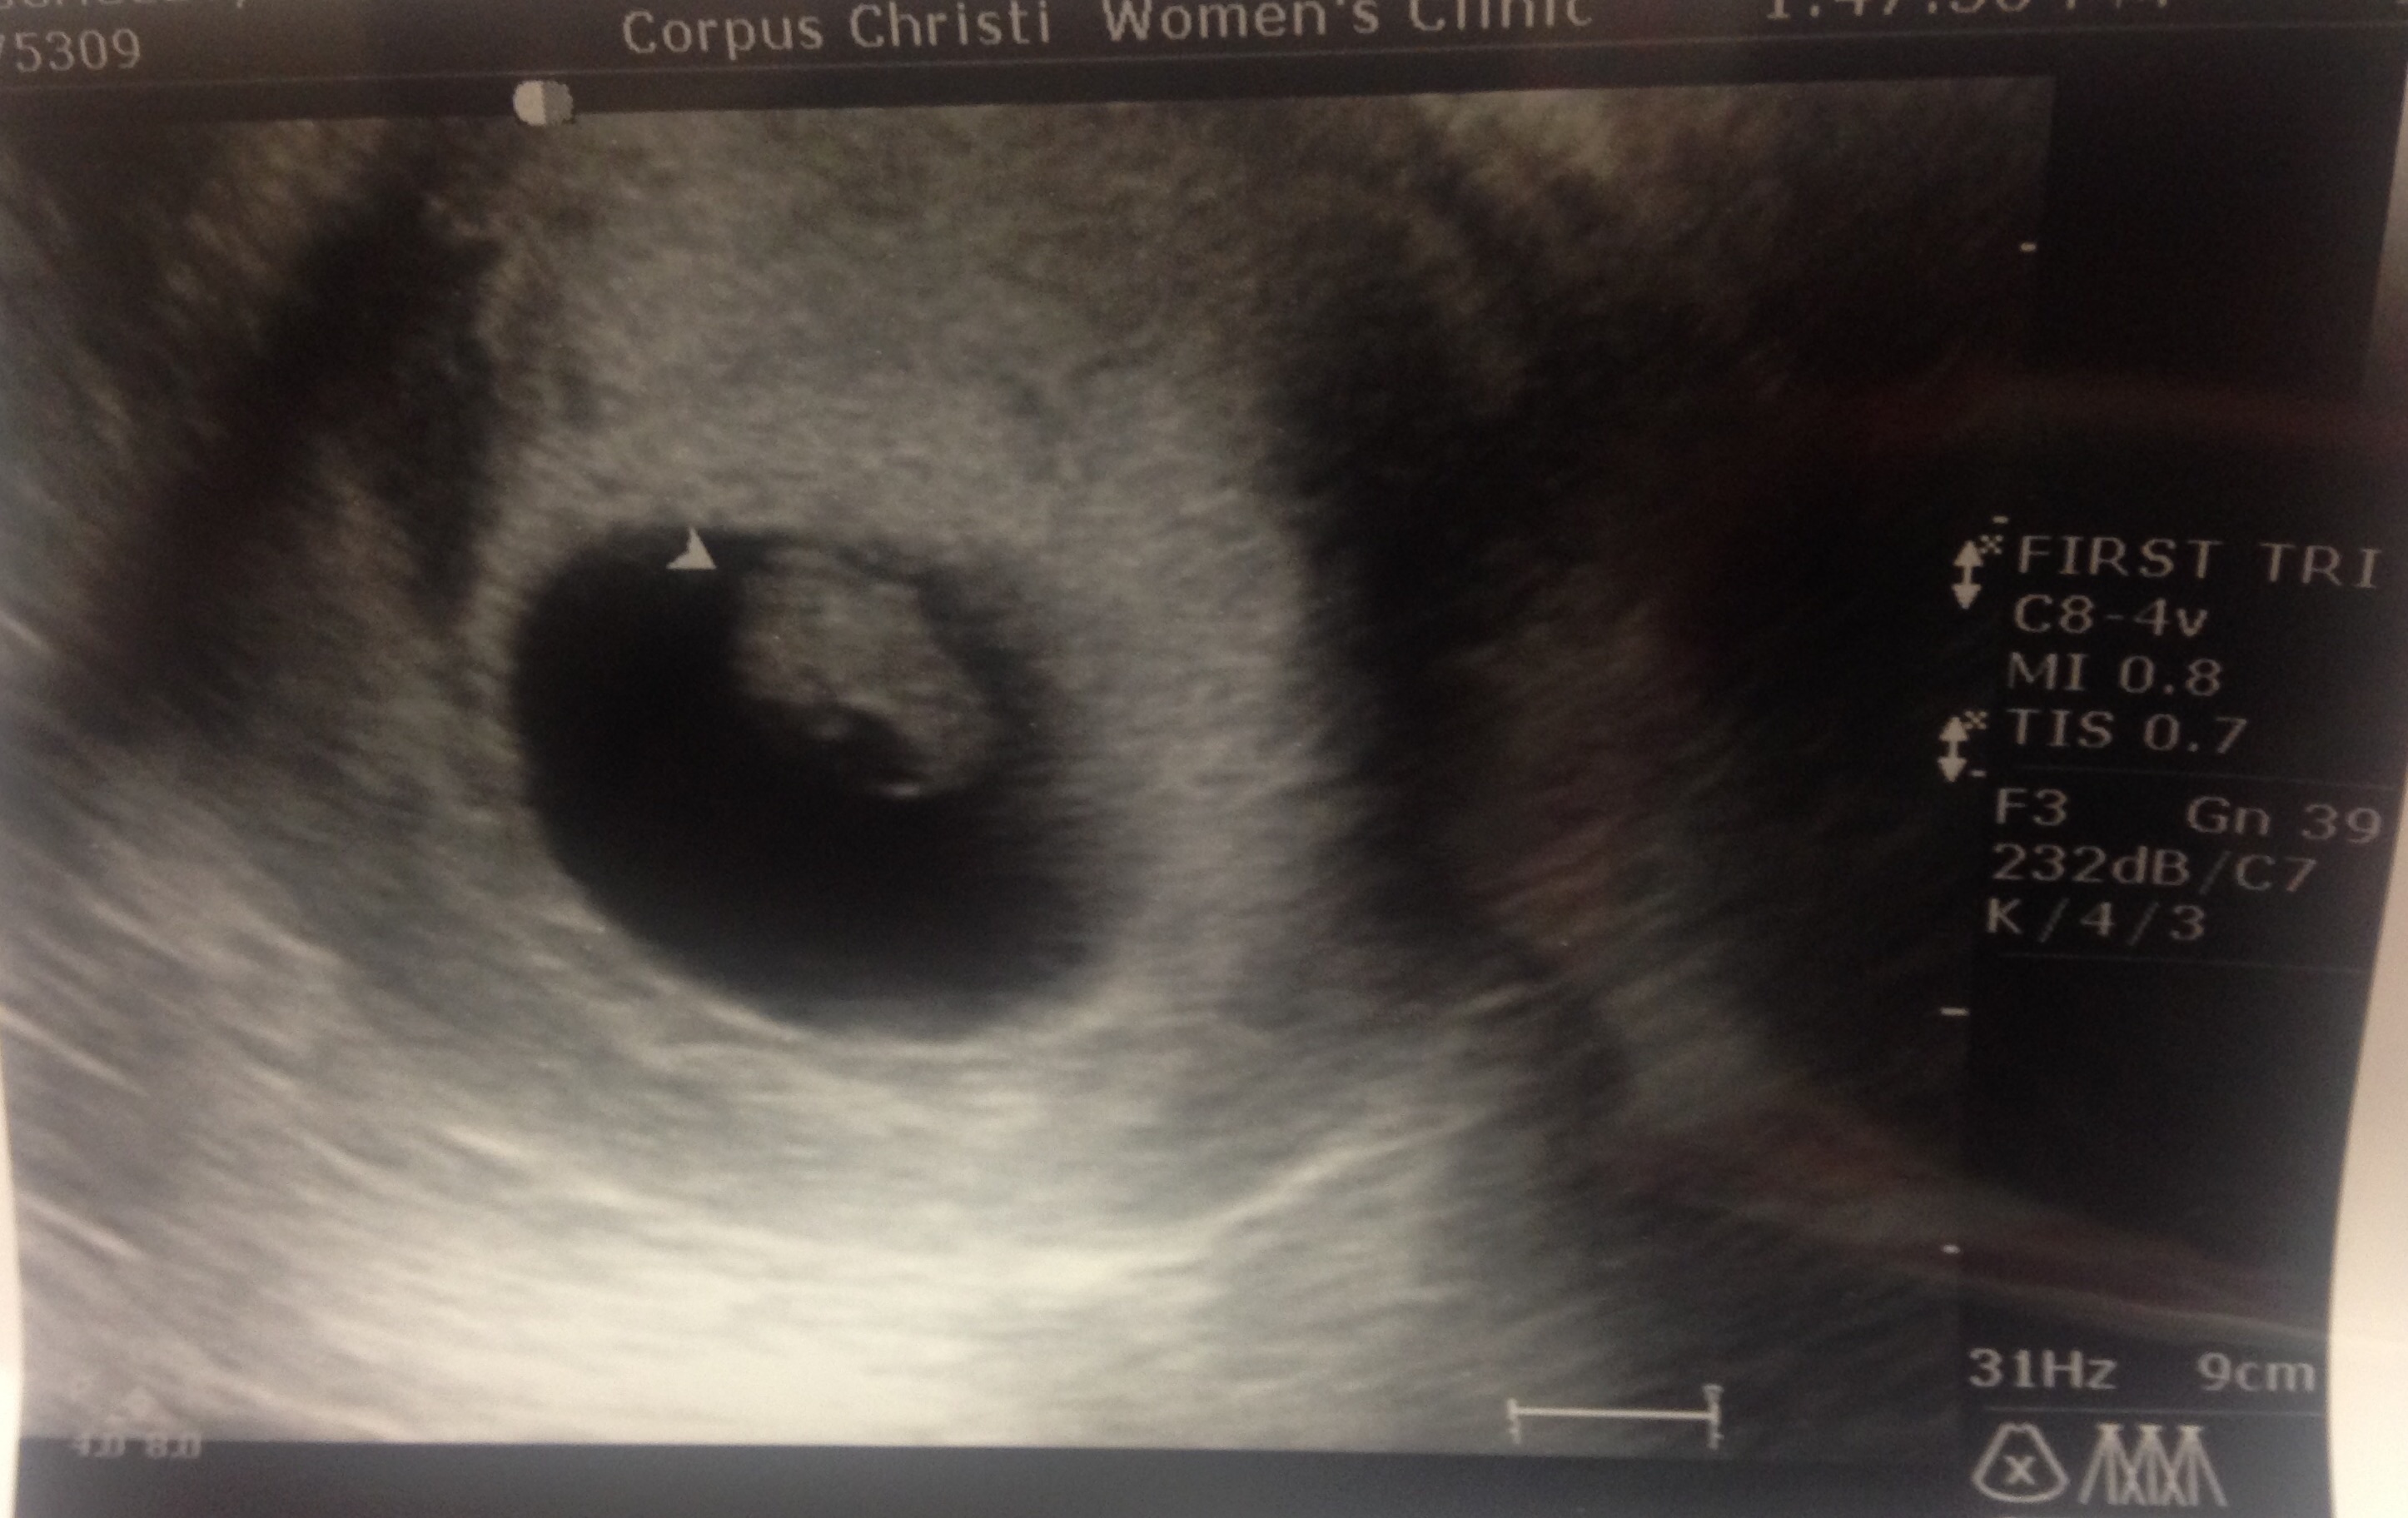

This is transvaginal at 10w2d

The thick white area to the bottom left seems to be the start of the placenta, so it looks just like the first picture in @adcc43 's example, so boy.